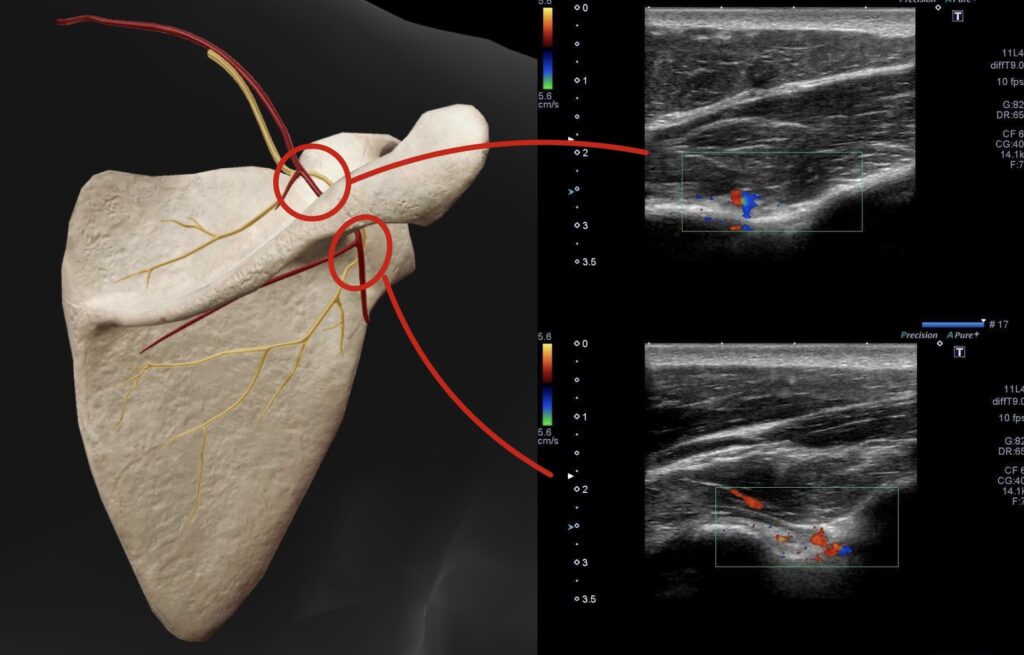

・超音波エコーで観察したところ、上腕二頭筋長頭腱周囲の炎症反応を確認した。

・初回は上腕二頭筋長頭腱の炎症鎮静と筋緊張の緩和を目的に超音波エコーガイド下で鍼施術を行った。

・3日後の来院時には痛みが少し残る。肩関節後方組織の柔軟性も低下していたため肩甲上神経に対し鍼施術を行った。